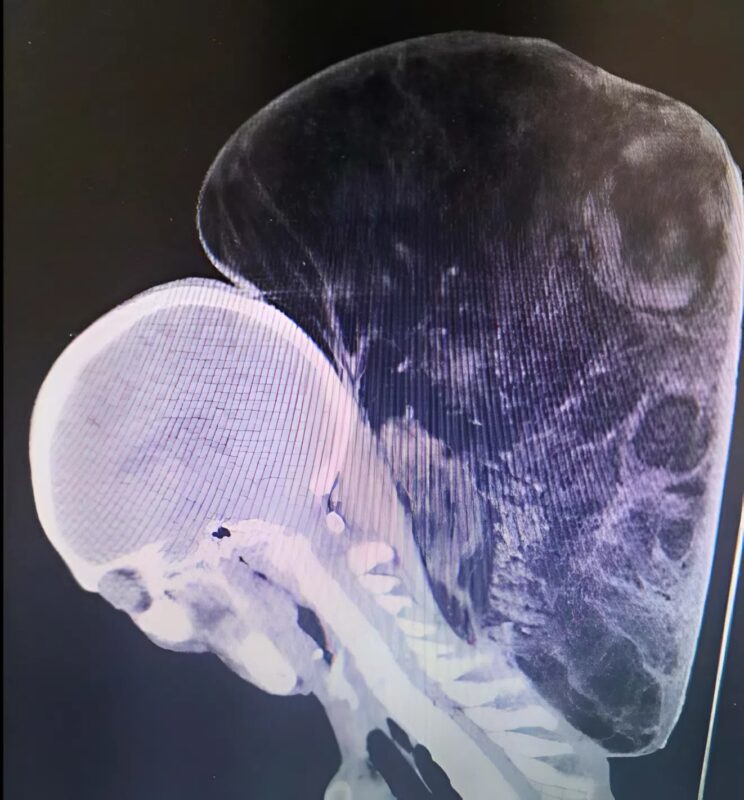

Surgery was scheduled immediately, though I’ll admit, I was terrified. Ten hours of delicate cutting, careful removal, and constant monitoring—every moment felt like a lifetime. The team worked meticulously, removing 95 percent of the mass. At 14.9 kilograms (33 pounds), it was more than just a tumor; it had become a burden I had carried for almost fifty years. 💪